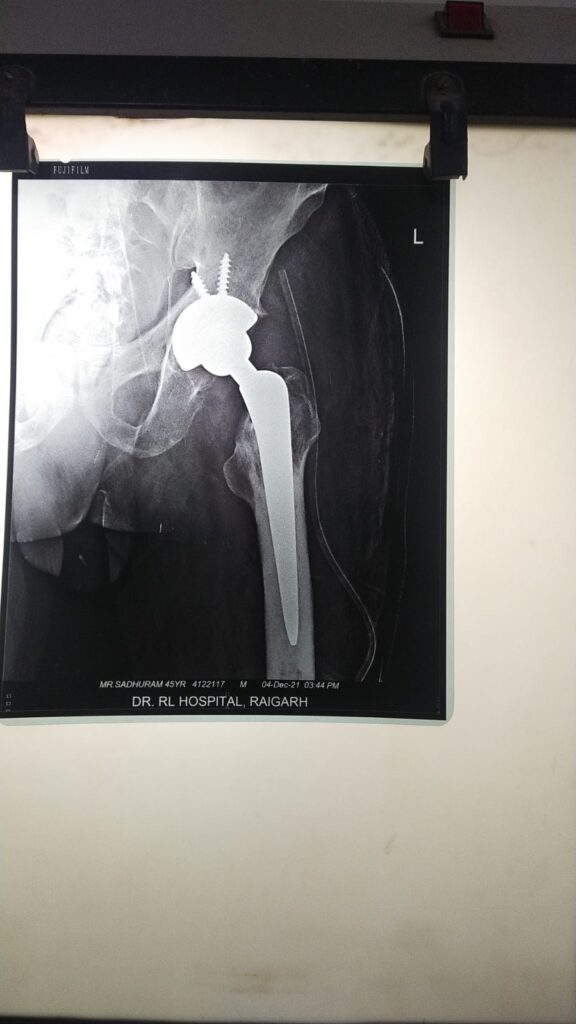

रायगढ़/शहर के प्रसिध्द डॉ. आर. एल. हॉस्पिटल जिले के लोगो के लिए वरदान साबित हो रहा है l हॉस्पिटल डायरेक्टर एंव अस्थि रोग विशेषज्ञ डॉ. प्रशांत के नेतृत्व मे हॉस्पिटल प्रतिदिन सैकड़ो मरीजों का मानवीय सेवा एंव सेवा भाव से सफल इलाज किया जा रहा है l इस बार फिर डॉ आर. एल. हॉस्पिटल के अस्थि रोग विभाग ने कूल्हे की दर्द से परेशान 45 वर्षीय पुरुष का सफल ऑपरेशन कर सफलता के झंडे गाड़ दिए l इस रेयर सर्जरी ने हॉस्पिटल का नाम सुनहरे पन्नों मे अंकित कर दिया है l तो वहीं यह अस्पताल मरीजों के लिए एक बड़ी आशा व

………………..विदित हो की 45 वर्षीय पुरुष (नाम न छापने के शर्त पर ) कूल्हे के दर्द से अत्यधिक पीड़ित था l पिछले छह : महीनों से लगातार असहनीय दर्द की शिकायत थी l इलाज के लिए पीड़ित व्यक्ति कई अस्पतालों का चक्कर काट चूका था l अंततः आशा के साथ पंहुचा डॉ. आर. एल. हॉस्पिटल………….पीड़ित व्यक्ति कई डॉक्टरो के इलाज पाश्चात् राहत नहीं मिलने पर अंततः विश्वास के साथ डॉ. आर. हॉस्पिटल मे हड्डी रोग विशेषज्ञ डॉ प्रशांत से मिलकर अपनी समस्या से अवगत कराया प्राथमिक उपचार